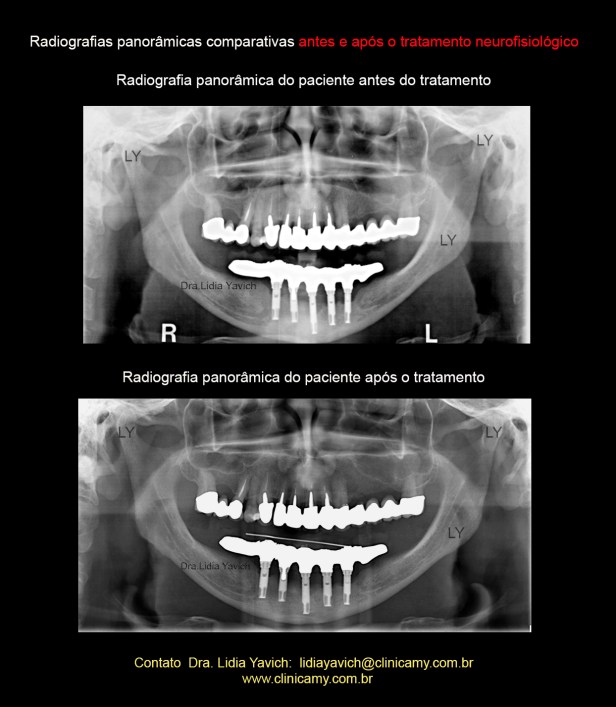

Radiografia panorâmica do paciente antes do tratamento neuromuscular fisiológico evidenciando o protocolo fixo sobre implantes na mandíbula.

O paciente tem este protocolo a mais de 18 anos.

O paciente relatou histórico de peri-implantite, e não tinha nenhuma imagem anterior a instalação dos implantes.

Radiografia panorâmica do paciente após o tratamento neuromuscular fisiológico.

Radiografias panorâmicas comparativas: antes do tratamento e após o tratamento neurofisiológico.